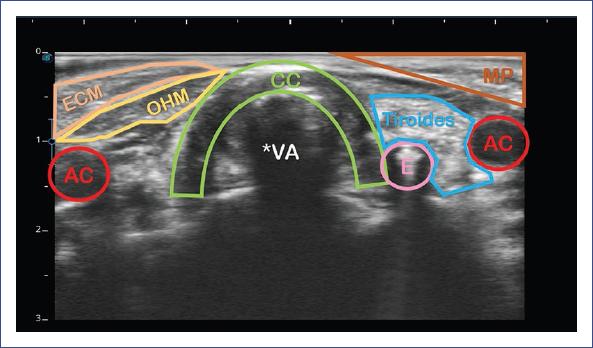

El IPFS y el LACWD se midieron con ultrasonido portátil Sonoscape E2 y transductor lineal (7-15 mHz) usando una configuración para tejidos blandos. Dicha medición se realizó por un intensivista pediatra ecografista crítico durante el protocolo de retiro del ventilador. Se obtuvieron tres mediciones y se promediaron. Las estructuras que se visualizan en la ecografía laríngea se muestran en la figura 1. La técnica de medición del IPFS se explica en la figura 2, y la medición del LACWD se explica en las figuras 3 y 4.

Figura 1 Estructuras anatómicas en la ecografía laríngea. AC: arteria carótida; CC: cartílago cricoides; E: esófago; ECM: esternocleidomastoideo; MP: músculo platisma; VA: vía aérea; OHM: músculo omohioideo.